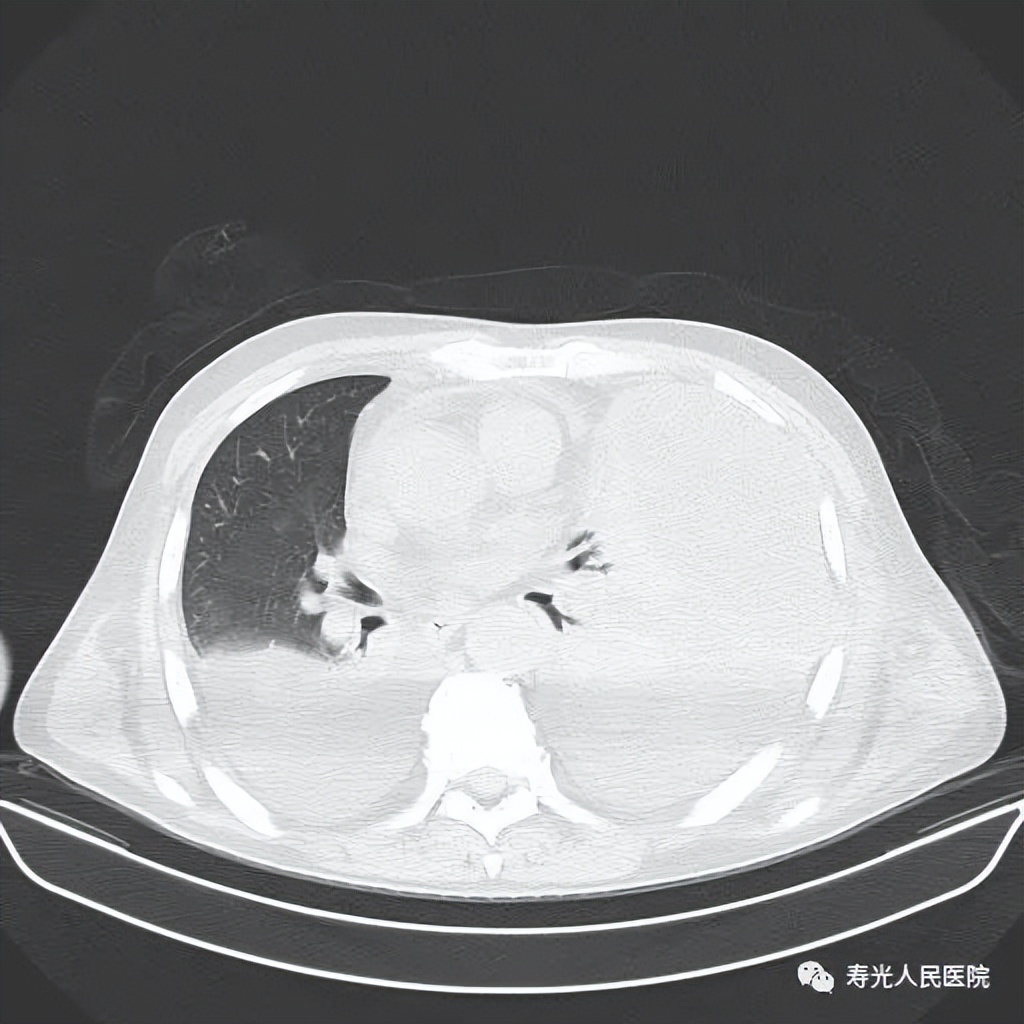

入科后,根据病情需要,即刻于右侧胸腔行微创引流术,左侧胸腔行闭式引流术,但复查胸部CT提示:左侧肺实变、不张。

入科时,患者双侧大量胸腔积液,左侧肺实变